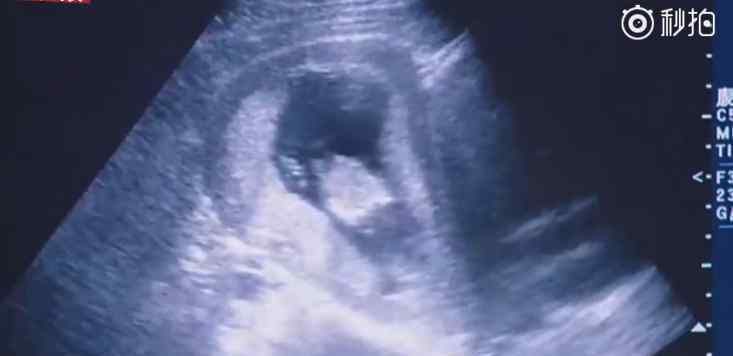

近日,印度一位母亲产下一名患有美人鱼综合症的婴儿,仅存活4小时。人鱼宝宝是一种极其罕见的先天性下肢畸形。患者天生腿内侧粘连,无法分离。乍一看像鱼尾,6-10万人中只发现一例。

专家解释,这是一种罕见的以肛门闭锁、泌尿生殖系统异常、下肢发育不全为特征的先天性畸形。